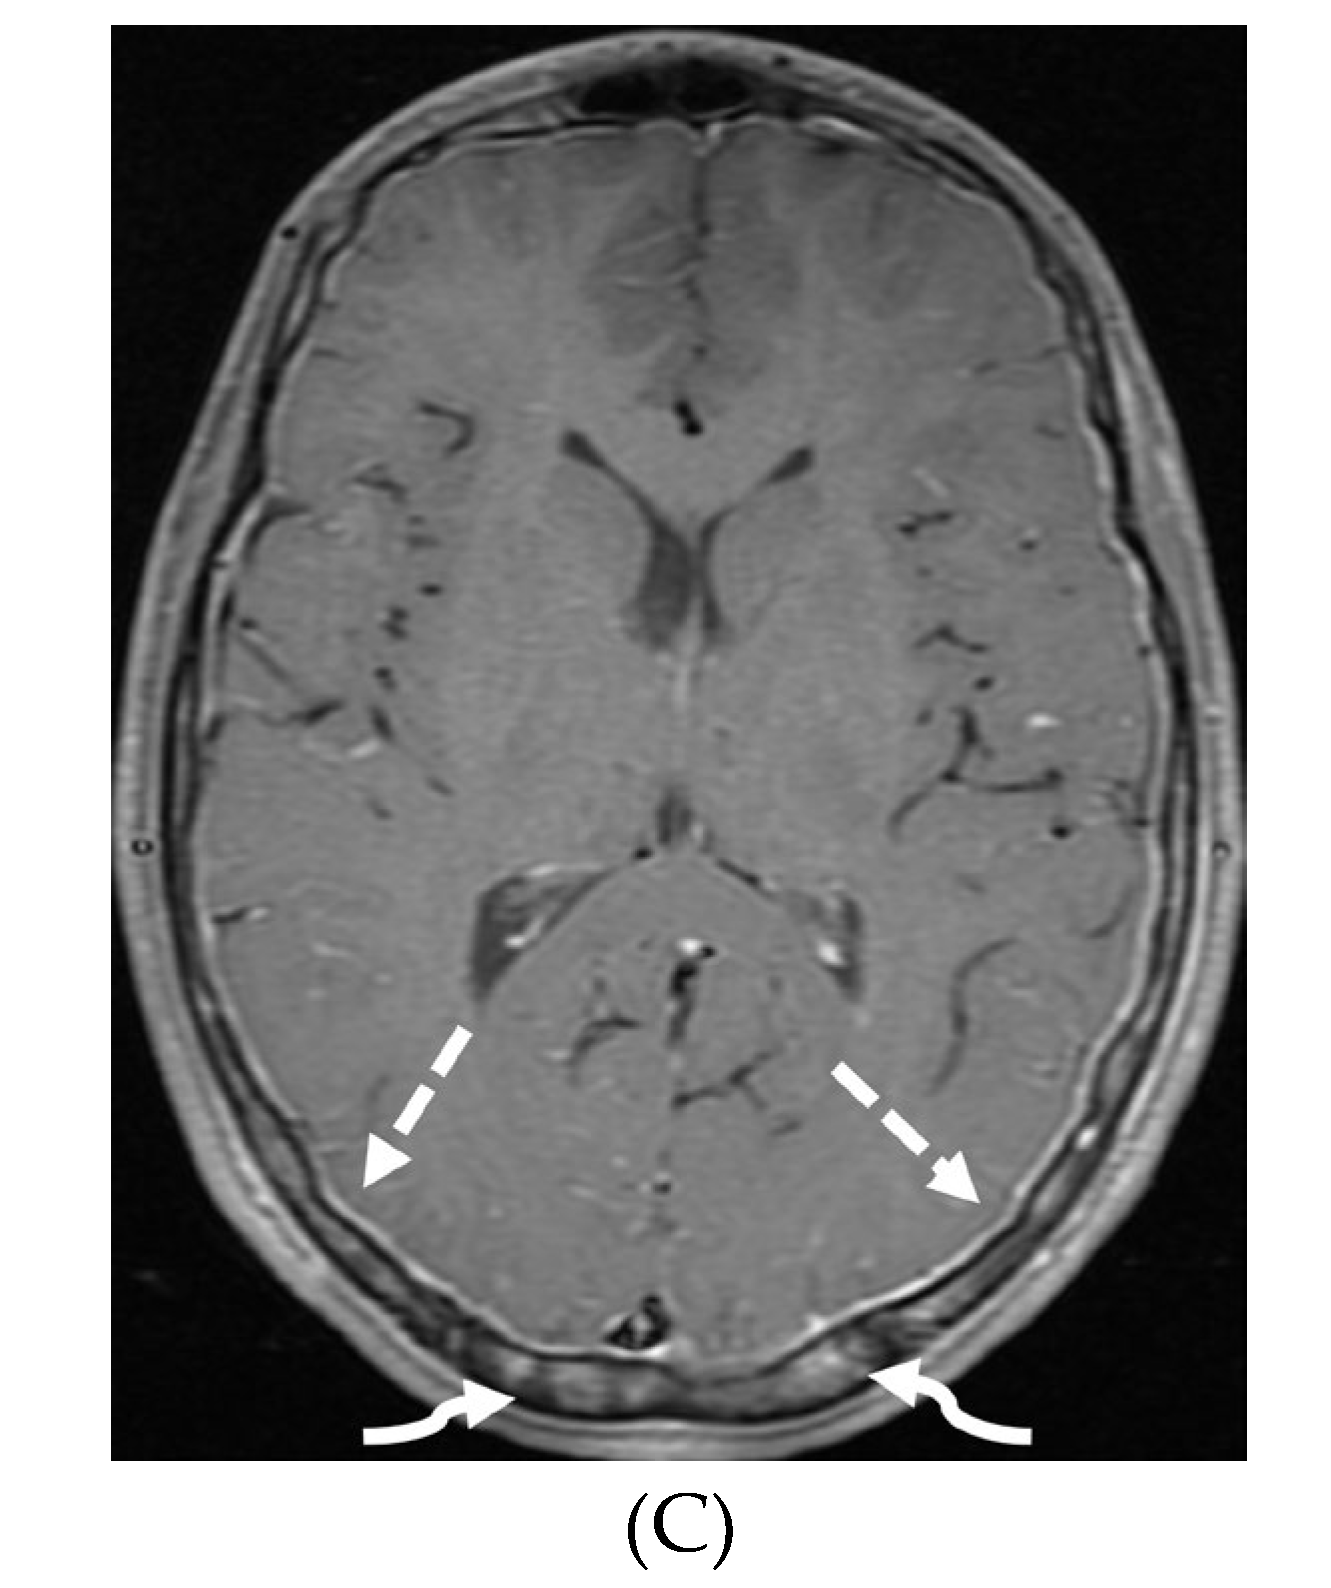

INTRACRANIAL HYPOTENSION (IH)

- Peterson EE, Riley BL, Windsor RB. Pediatric Intracranial Hypotension and Post-Dural Puncture Headache. Semin Pediatr Neurol. 2021 Dec;40:100927. Epub 2021 Sep 3. PMID: 34749914. [CrossRef]

- Schievink WI, Maya MM, Louy C, Moser FG, Sloninsky L. Spontaneous intracranial hypotension in childhood and adolescence. J Pediatr. 2013 Aug;163(2):504-10. Epub 2013 Feb 28. PMID: 23453548. [CrossRef]

- Shah LM, McLean LA, Heilbrun ME, Salzman KL. Intracranial hypotension: improved MRI detection with diagnostic intracranial angles. AJR Am J Roentgenol. 2013 Feb;200(2):400-7. PMID: 23345364. [CrossRef]

- Yuh EL, Dillon WP. Intracranial hypotension and intracranial hypertension. Neuroimaging Clin N Am. 2010 Nov;20(4):597-617. PMID: 20974378. [CrossRef]

- Medina JH, Abrams K, Falcone S, Bhatia RG. Spinal imaging findings in spontaneous intracranial hypotension. AJR Am J Roentgenol. 2010 Aug;195(2):459-64. PMID: 20651205. [CrossRef]